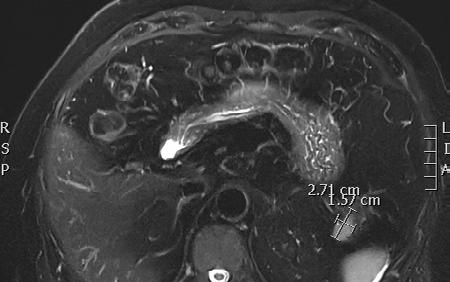

TOOWOOMBA

Conference Sessions

Official Welcome and Opening

Oncology - Paul Roach, Louise Emmett, Bital Savir-Baruch, John Buscombe, Dale Bailey, Grace Kong

ANZSNM President, Karen Jones with EANM representatives, Michel

Cardiology Non-MPI - Nathan Better, Sam Wright, Prem Soman, Dinesh Sivaratnam

President's Dinner

Koole, Felix Mottaghy and Sylvia Marchetti

Musculoskeletal Imaging

Claire Owen, Bonnia Liu, Malcom Hogg